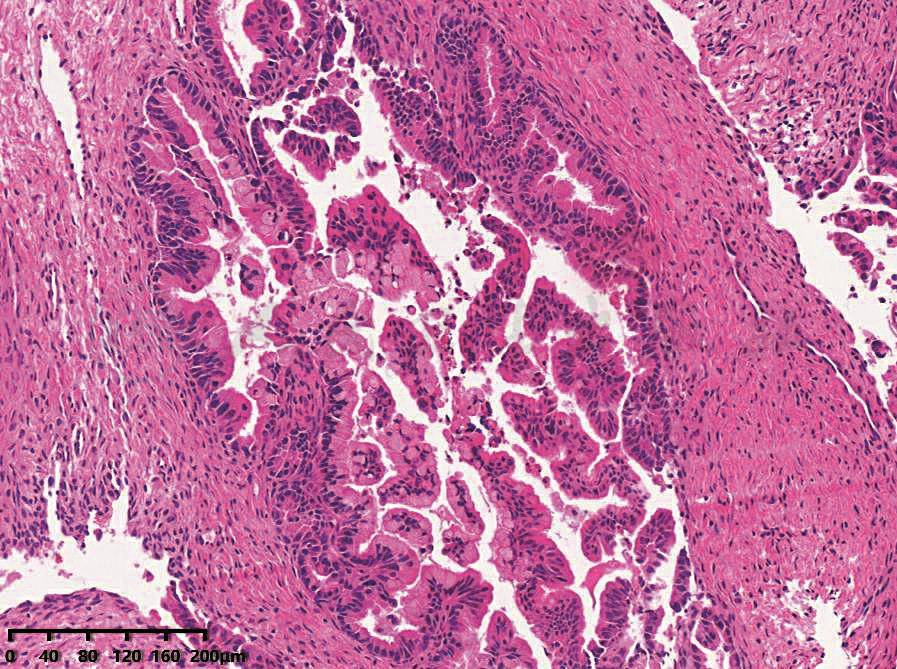

较交界性浆液性肿瘤复杂,为多房性。可见到囊壁增厚区或出现乳头,而大多数乳头细小,也可呈息肉样。镜下特点:①上皮复层化达2~3层,但不超过3层,伴有乳头和上皮簇形成;②细胞轻度、中度非典型形,黏液分泌减少,可见杯状细胞;③核分裂象每10个高倍镜视野内不超过5个;④肿瘤细胞不侵及间质(图1)。

图1 卵巢交界性黏液性肿瘤